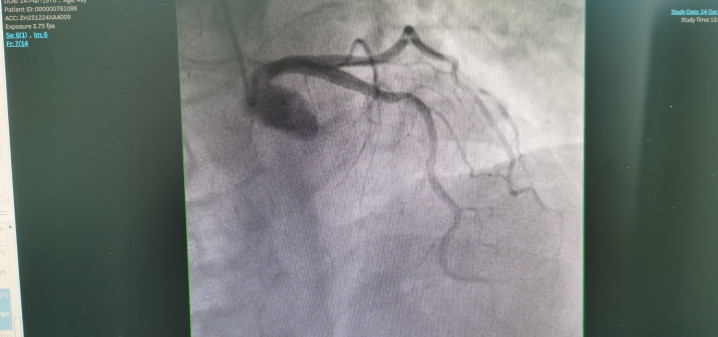

冠状动脉造影